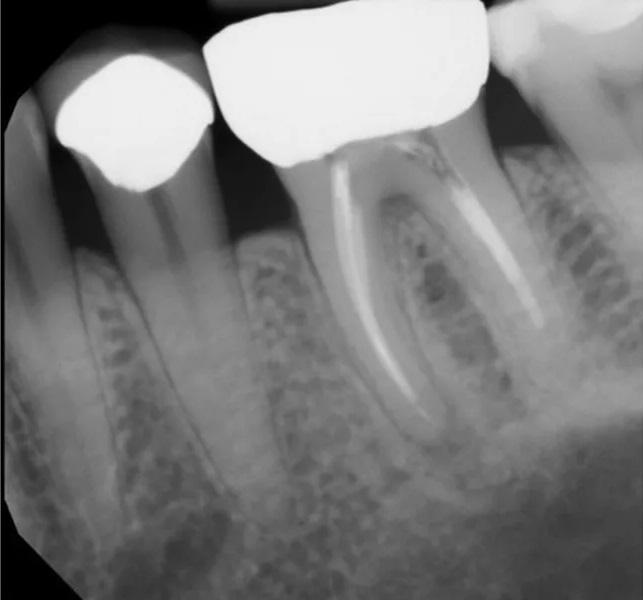

К другим значимым причинам неудач эндодонтического лечения относятся пропущенные или необработанные каналы, в которых сохраняются бактерии, способствующие реинфекции. Неполноценная механическая и медикаментозная обработка каналов, а также неадекватная обтурация также часто приводят к неудаче, поскольку создают условия для выживания и колонизации микроорганизмов в системе каналов. Кроме того, ятрогенные ошибки, такие как перелом инструментов, перфорации или коронковая негерметичность вследствие некачественных реставраций, могут нарушать герметичность системы корневых каналов, создавая пути для проникновения бактерий и последующего развития инфекции (фото 1). В результате формируются периапикальные очаги, обусловленные иммунным ответом организма пациента на микробные и воспалительные факторы.

Фото 1. Клинический случай 1. Периапикальная рентгенограмма, демонстрирующая периапикальную патологию, связанную с зубом 36, обусловленную неустраненными осложнениями первичного нехирургического эндодонтического лечения, включая отлом инструмента и коронковую негерметичность. Неустраненные осложнения могут приводить к неудаче эндодонтического лечения и усложнять проведение нехирургического повторного лечения, делая его исходы менее предсказуемыми.